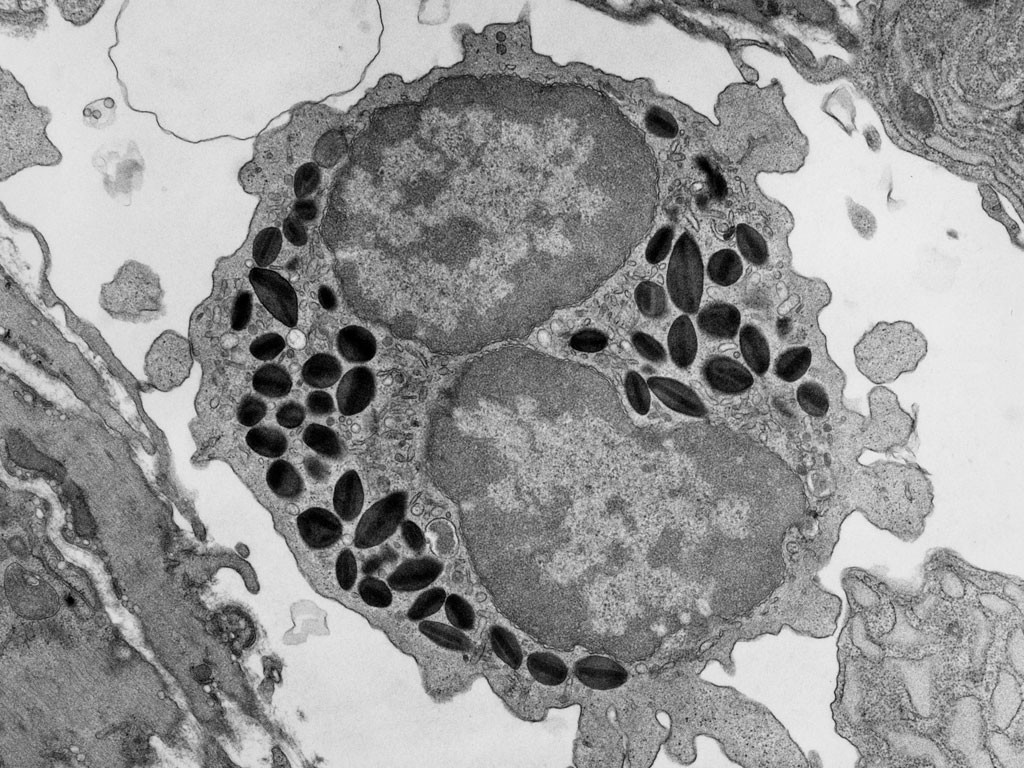

Eosinofiele granulocyt Eosinofiele granulocyt

eosinofiel eosinofiel

Dip quick, diff quick kleuring Eosinofiele granulocyten in biopt

eo's in Diff-quick eosinofiel in biopt

Foto rechtsboven: Peter Takizawa - Department of Cell Biology - University of Yale.